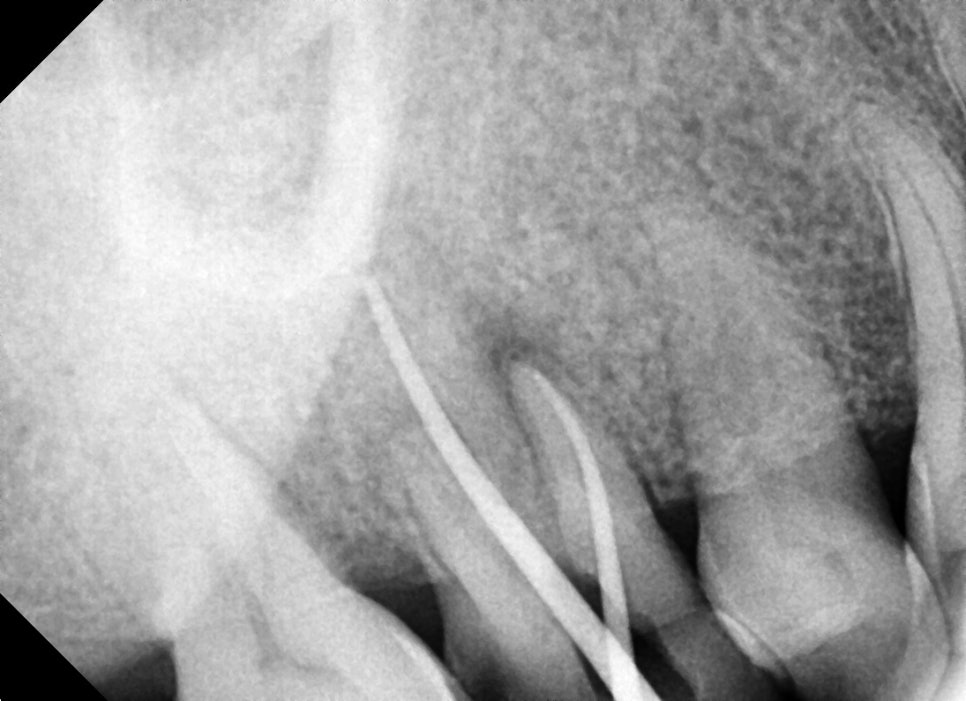

임시로 사용했을 때의 사진입니다.

다행히 여러 번의 신경관 소독을 통해 입천장 쪽의 고름 주머니는 사라지고, 통증도 줄어들으셨지만

추후 염증원의 재발이 일어난다면 다시 염증반응이 일어날 수 있음을 설명드렸습니다.

정기적으로 내원하셔서 구강위생을 유지하시는 것도 중요하지만

다른 치아들을 지키기 위해서는 상실된 부위를 수복하는 것도 중요한 작업입니다.

앞으로 꾸준한 정기체크를 하며 지켜봐야 할 필요가 있습니다.

장기간 사용하시면 좋겠지만, 상황이 허락하는 한 관리하며 잘 쓰셨으면 좋겠습니다.^^